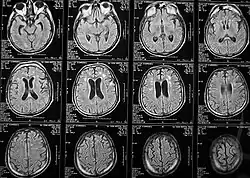

Томография позволяет визуализировать с высоким качеством головной, спинной мозг и другие внутренние органы. Современные технологии МРТ делают возможным неинвазивно (без вмешательства) исследовать работу органов — измерять скорость кровотока, тока спинномозговой жидкости, определять уровень диффузии в тканях, видеть активацию коры головного мозга при функционировании органов, за которые отвечает данный участок коры (функциональная магнитно-резонансная томография — фМРТ).

Функциональная МРТ (фМРТ) — метод картирования коры головного мозга, позволяющий определять индивидуальное местоположение и особенности областей мозга, отвечающих за движение, речь, зрение, память и другие функции, индивидуально для каждого пациента.

Суть метода заключается в том, что при работе определённых отделов мозга кровоток в них усиливается.

В процессе проведения ФМРТ пациенту предлагается выполнение определённых заданий, участки мозга с повышенным кровотоком регистрируются, и их изображение накладывается на обычную МРТ мозга.